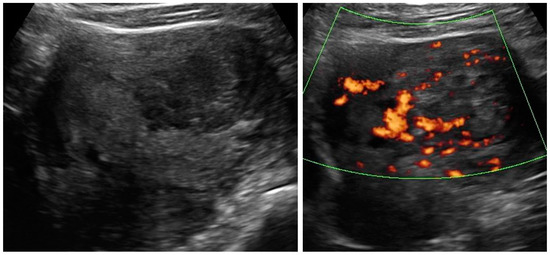

| Case Number (Age, Years Old) | Ultrasound Diagnosis of Uterine Lesion | Figure | Initial Treatment/ Histological Diagnosis Required (Doctor’s Decision) | Initial Patient’s Willingness to Undergo Surgery for the Uterine Lesion | Histology from Core Needle Biopsy | Patient Decision to Undergo Surgery for the Uterine Lesion | Histology from Definitive Surgery | Did Core Needle Biopsy Provided Additional Information to Ultrasound | Did Core Needle Biopsy Provided Useful Information for the Clinical Management |

| 1 (44) | Typical uterine lesion (myoma) | Figure A1 | No | Yes | Leiomyoma, cellular variant (UG-TUC core needle biopsy) | Yes (lesion enlarged during follow-up) | Leiomyoma, cellular variant | No | Yes |

| 2 (36) | Sarcoma suspicion | Figure A2 | Yes | Tumorectomy, uterus preservation (young age) | LMS (UG-TUC core needle biopsy) | Yes | LMS | No | Yes |

| 3 (37) | Atypical uterine lesion | Figure A3 | Yes | No | Lipoleiomyoma (UG-TUC core needle biopsy) | No | - | Yes | Yes |

| 4 (56) | Atypical uterine lesion | Figure A4 | Yes | Yes | Leiomyoma (transvaginal ultrasound guided core needle biopsy) | Yes | Leiomyoma and adenomyosis | Yes | No |

| 5 (50) | Atypical uterine lesion (metastatic adenocarcinoma G3 in inguinal lymph node) | Figure A5 | Yes | No | Leiomyoma (UG-TUC core needle biopsy) | No | Uterus / tumor not resected because primary urological carcinoma was diagnosed | Yes | Yes |

| 6 (38) | Atypical uterine lesion | Figure A6 | Yes | No | Leiomyoma, epithelioid variant (UG-TUC core needle biopsy) | Yes (lesion enlarged during follow-up) | Leiomyoma, epithelioid variant | Yes | Yes |

| 7 (29) | Atypical uterine lesion | Figure A7 | Yes | Yes | Leiomyoma (UG-TUC core needle biopsy) | Yes | Leiomyoma with signs of degenerations | Yes | Yes |

| 8 (52) | Atypical uterine lesion | Figure A8 | Yes | Yes | Total abdominal hysterectomy performed without core need biopsy, because of patients age and lesion ultrasound pattern recognition. Note: frozen section result: leiomyoma | Yes | STUMP | - | - |